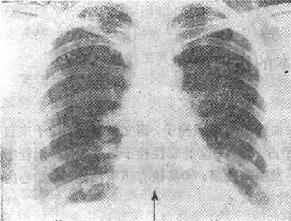

图116-1 肺梗死

(三)胸片可以显示肺栓塞的某些X线表现 ①一侧膈肌升高,大约有一半的急性肺栓塞的患者有此表现(肺容积的减少);②约有30%~50%的肺栓塞患者有一过性的肺实质浸润;③肺不张(约20%),但机制不清;④胸膜渗出,有1/3的患者出现;⑤有两个特异性的X线表现:Hampten’s驼峰征,为一个肺内的实变征,呈圆形圆顶状轮廓,顶部指向肺门,位于肺肋膈角区或后肋膈窦区;Wamptark’s征,栓塞侧近侧肺动脉扩张而远侧缺乏之灌注(无血管区),这两种特异的征象是很少见的;⑥肺动脉主干扩张、肺动段突出,甚至右心室增大。